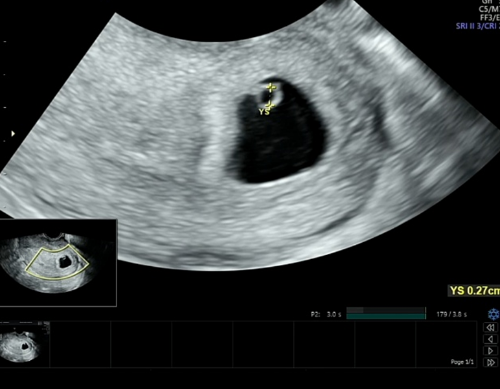

그리고 다녔던 난임병원에 다시 들러 6주 0일 아기집, 난황, 심장소리를 확인했습니다.

난황은 동그랗게 다이아몬드반지처럼 보인답니다.

난황에 가려져 잘 보이지 않는 아기, 아기는 지금 매우매우 작은 0.38cm의 모습을 하고 있답니다.